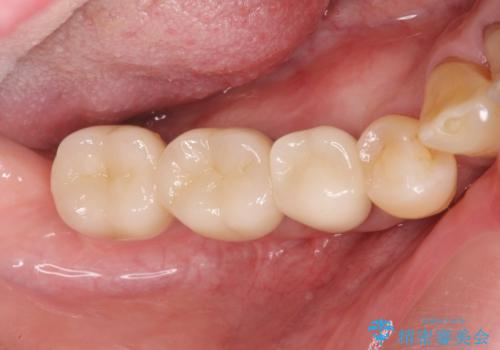

歯周病により抜去した歯のインプラント治療

長期的な予後の見込めない奥歯の抜去を行い、骨と歯ぐきの治癒を待ち、インプラント治療を計画します。

- 88万円(インプラント2本分)費用は治療当時の料金となります